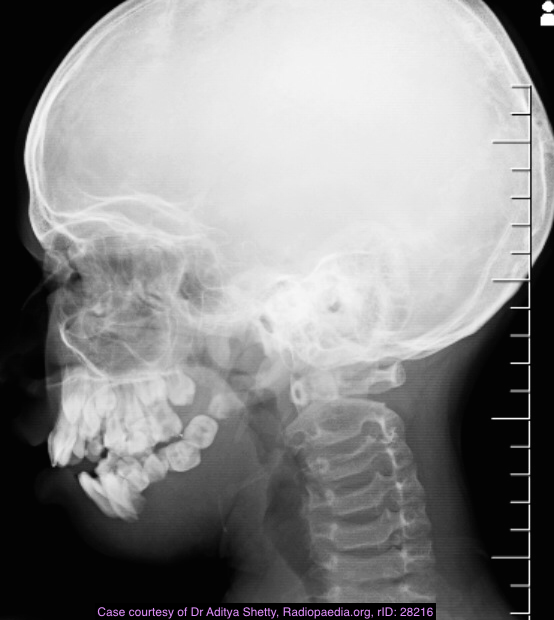

Gorham disease or vanishing bone disease is a poorly understood rare skeletal condition which manifests with massive progressive osteolysis along with a proliferation of thin walled vascular channels. The disease starts in one bone but may spread to involve adjacent bony and soft tissue structures.

skull 2

Plain radiograph and CT

intramedullary or subcortical lucent foci may be the earliest manifestation 1

this progresses to profound osteolysis with resorption of affected bone and lack of compensatory osteoblastic activity or periosteal reaction